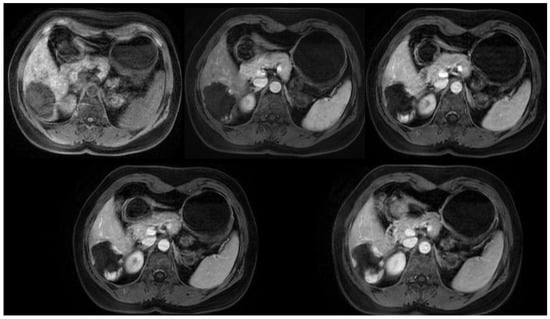

4.5. Magnetic Resonance Imaging

- Mamone, G.; Di Piazza, A.; Carollo, V.; Cannataci, C.; Cortis, K.; Bartolotta, T.V.; Miraglia, R. Imaging of hepatic hemangioma: From A to Z. Abdom. Radiol. 2020, 45, 672–691. [Google Scholar] [CrossRef] [PubMed]

- Caseiro-Alves, F.; Brito, J.; Araujo, A.E.; Belo-Soares, P.; Rodrigues, H.; Cipriano, A.; Sousa, D.; Mathieu, D. Liver haemangioma: Common and uncommon findings and how to improve the differential diagnosis. Eur. Radiol. 2007, 17, 1544–1554. [Google Scholar] [CrossRef] [PubMed]

- Danet, I.M.; Semelka, R.C.; Braga, L.; Armao, D.; Woosley, J.T. Giant hemangioma of the liver: MR imaging characteristics in 24 patients. Magn. Reson. Imaging 2003, 21, 95–101. [Google Scholar] [CrossRef]

- Yu, J.S.; Kim, M.J.; Kim, K.W.; Chang, J.C.; Jo, B.J.; Kim, T.H.; Lee, J.T.; Yoo, H.S. Hepatic cavernous hemangioma: Sonographic patterns and speed of contrast enhancement on multiphase dynamic MR imaging. Am. J. Roentgenol. 1998, 171, 1021–1025. [Google Scholar] [CrossRef]

- Sousa, M.S.C.; Ramalho, M.; Herédia, V.; Matos, A.P.; Palas, J.; Jeon, Y.H.; Afonso, D.; Semelka, R.C. Perilesional enhancement of liver cavernous hemangiomas in magnetic resonance imaging. Abdom. Imaging 2014, 39, 722–730. [Google Scholar] [CrossRef] [PubMed]